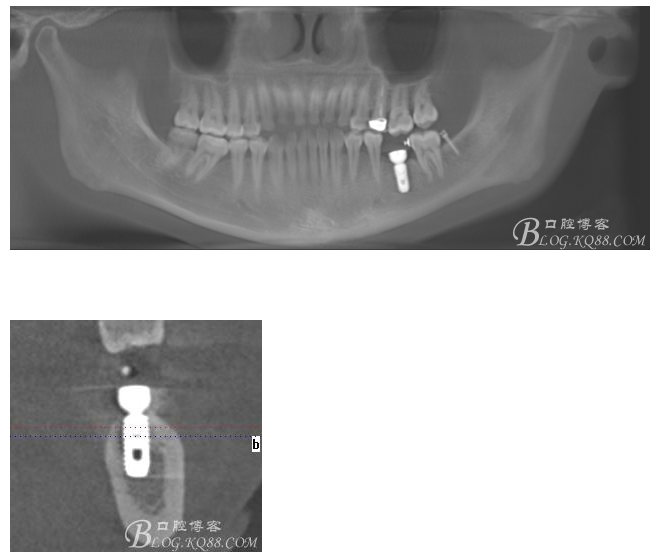

術(shù)前CT

術(shù)后CT片